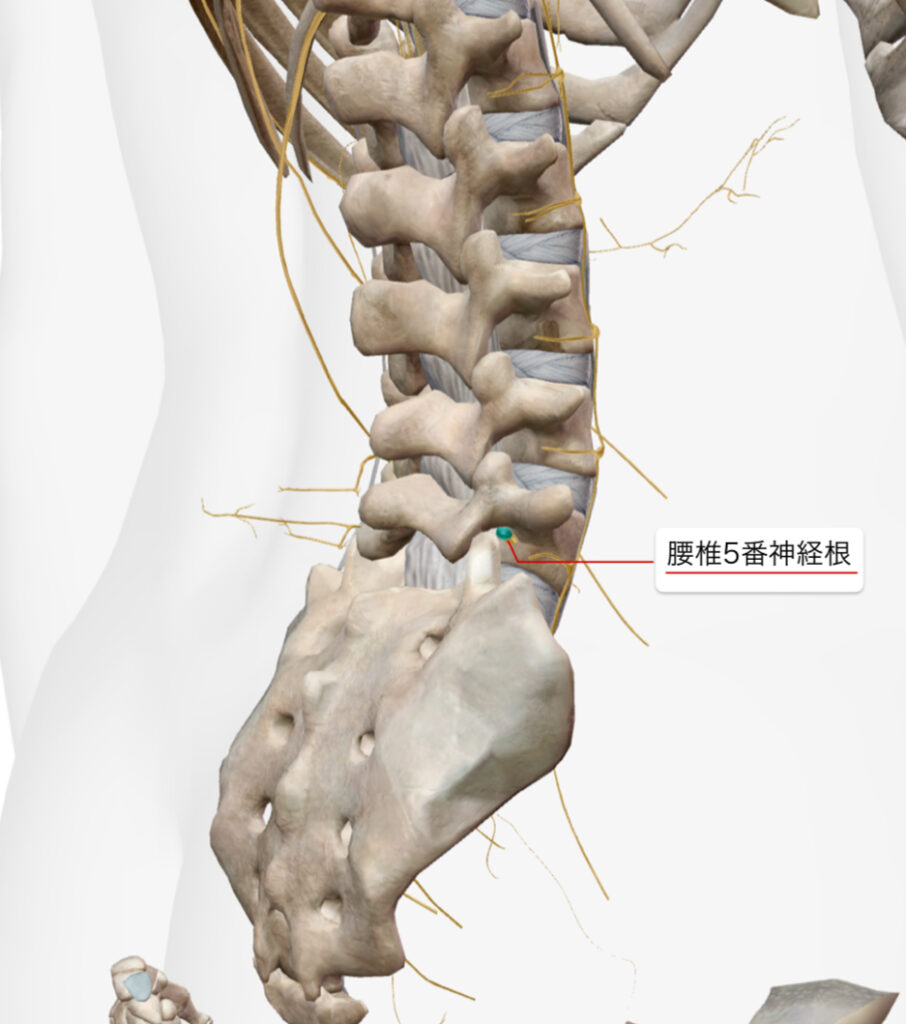

・超音波エコーで観察したところ、腰椎5番目・仙骨1番の椎間関節と仙腸関節の靭帯周囲にファシアの重責がみられた。

・坐骨神経痛の原因が腰椎5番目の神経根周囲の可能性があったため、エコーガイド下L5/S1神経根と後仙腸靭帯に対しエコー下鍼施術、鍼通電を行った。